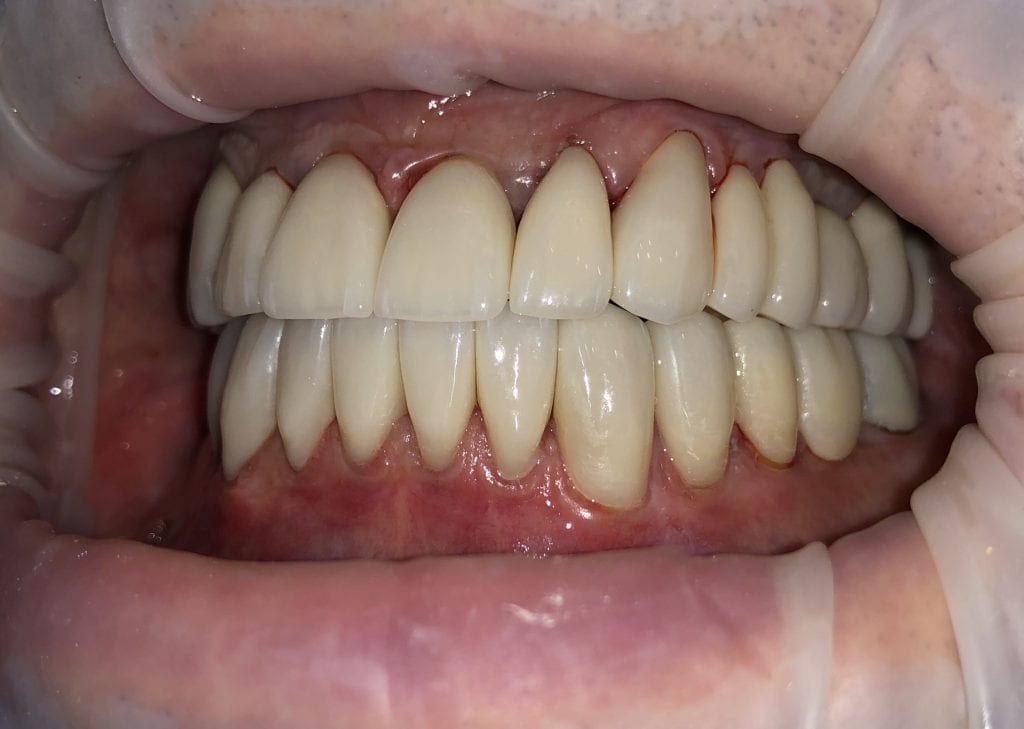

IMMEDIATE POST-OP PHOTOS AND VIDEO WITH IPHONE CAMERA